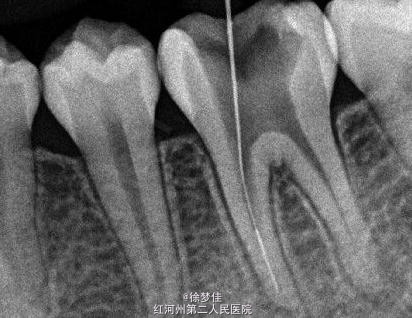

左下6近中根管断针X-P,断针长度约4MM, 根尖慢性炎症

插针确定断针根管,为近舌根管,插针有阻力,EDTA封存一周复诊。打开根管上部通路,根管大量清洗剂等冲洗,找到后,直接用超声根管搓15号带出断针。